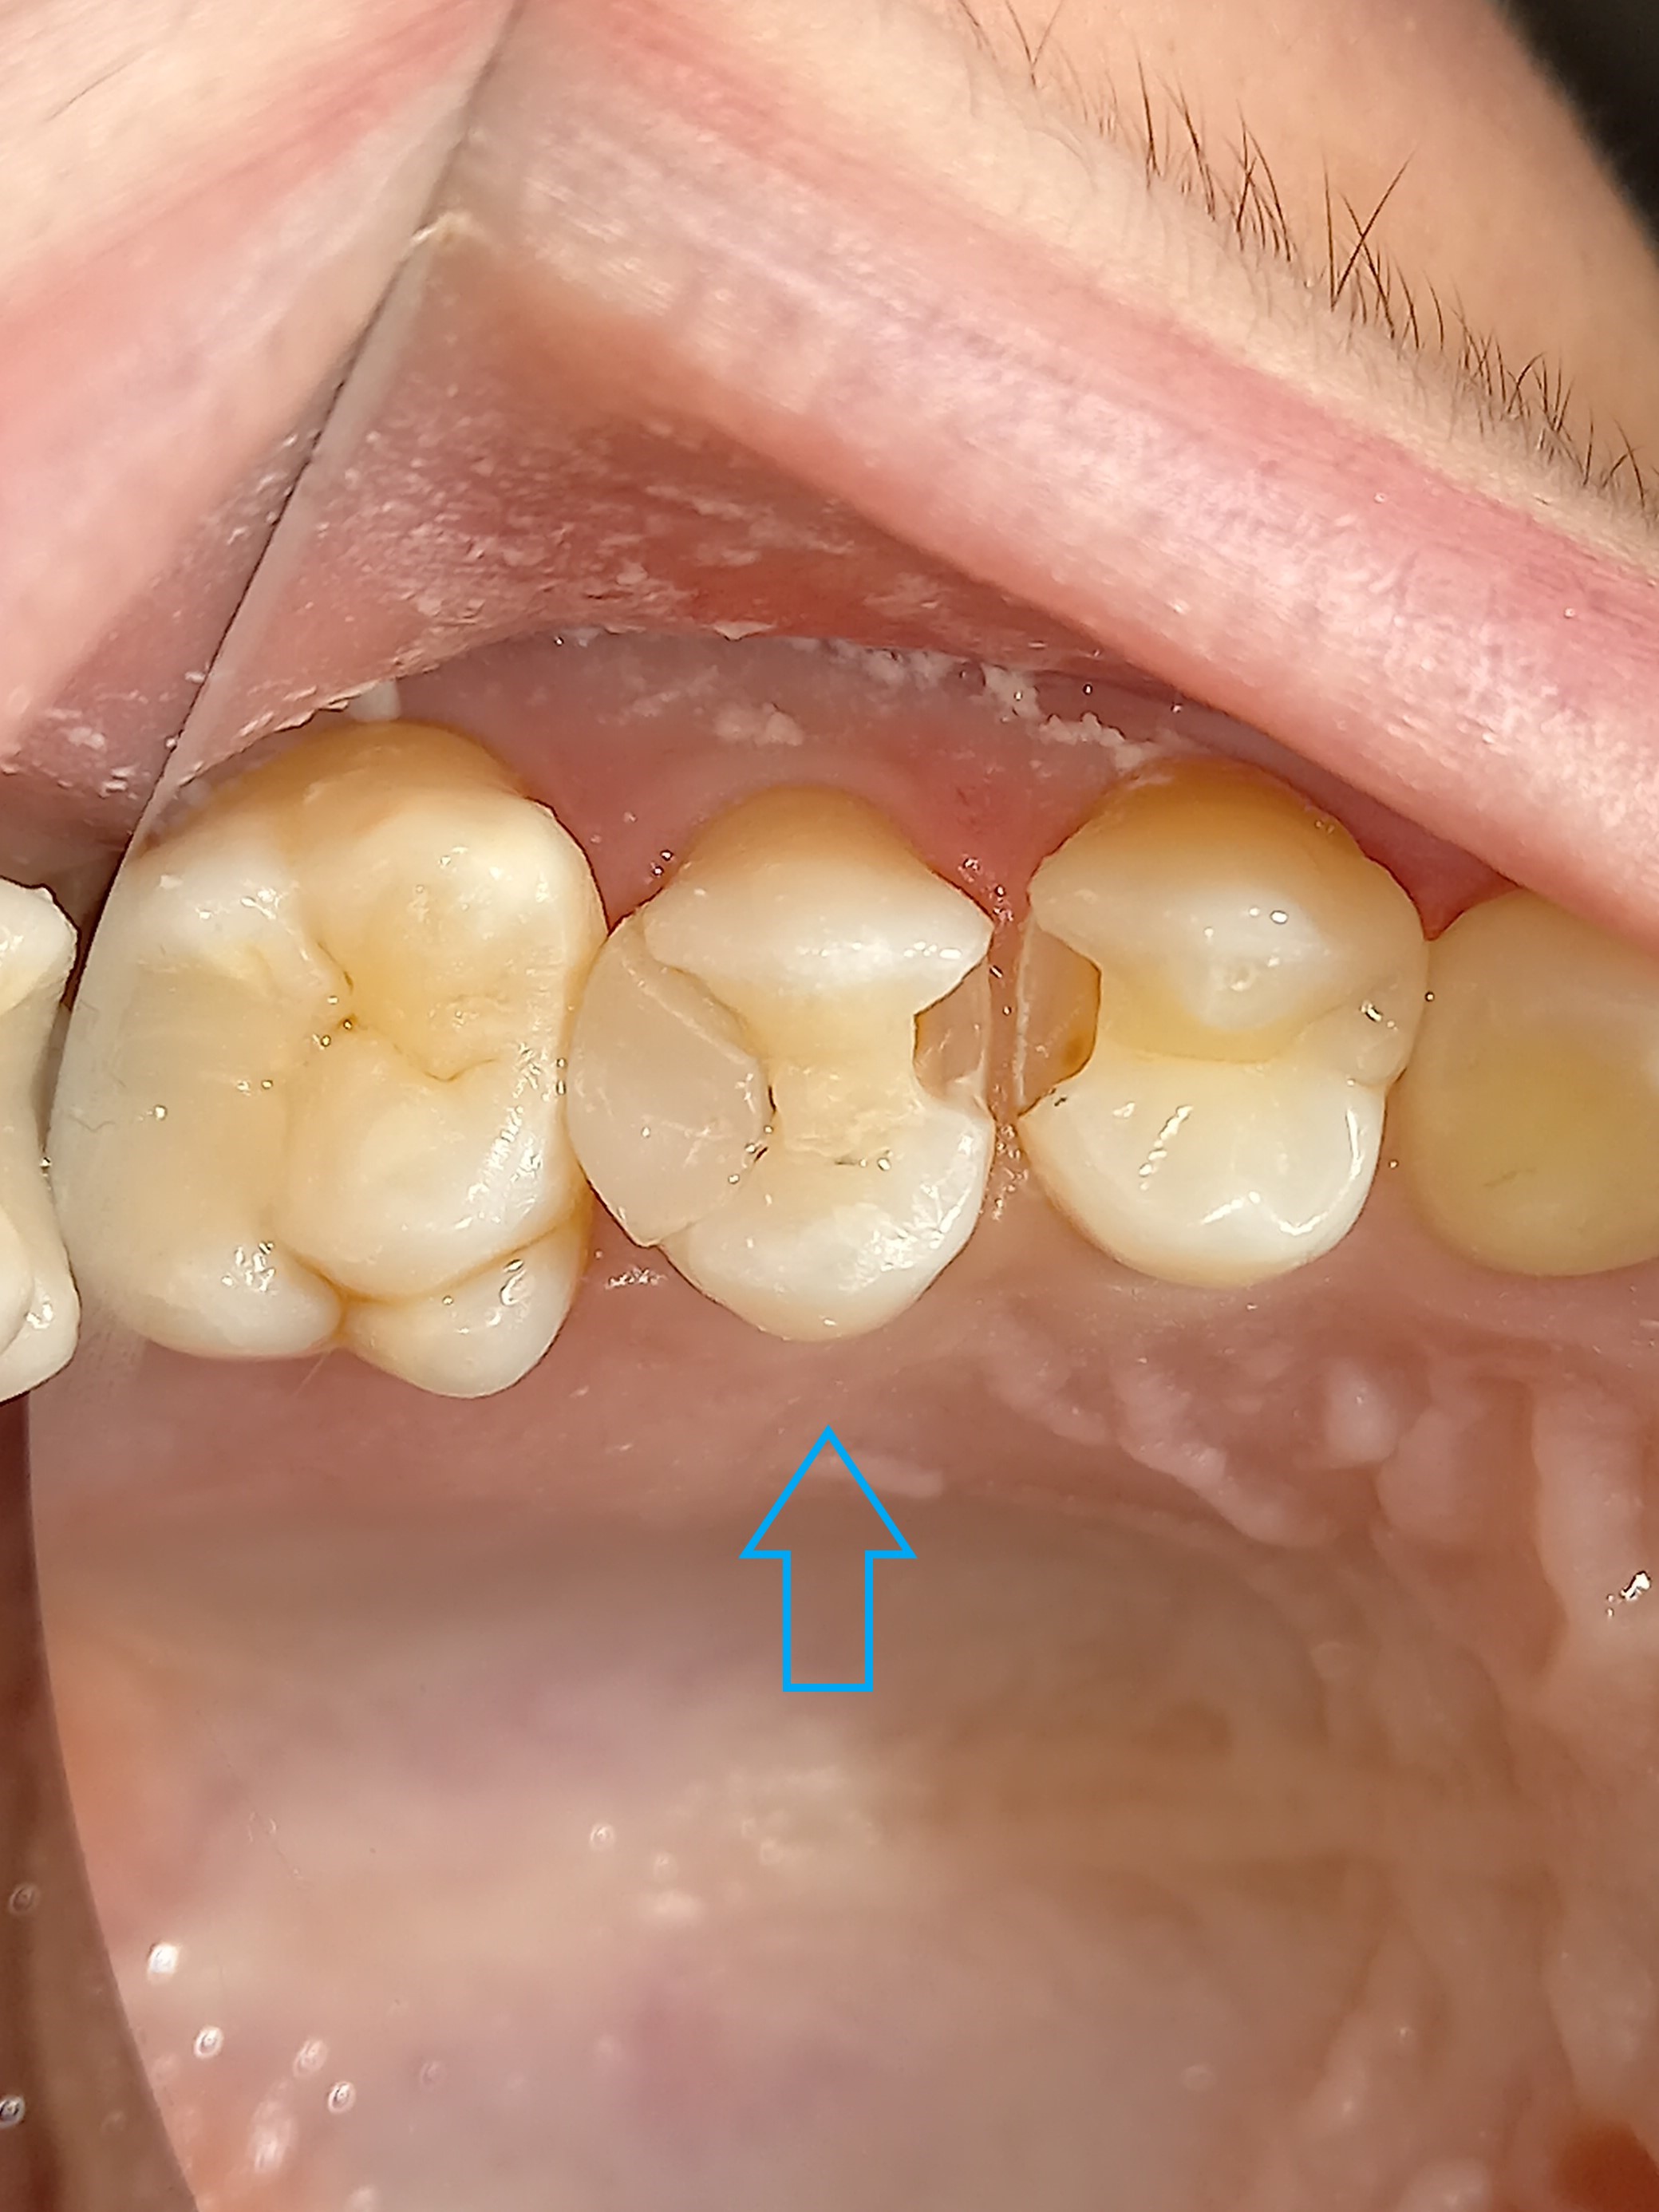

Αρχική κλινική εικόνα του μεγάλου οδοντικού ελλείμματος

Τελική κλινική εικόνα του ολοκεραμικού επένθετου στο γομφίο